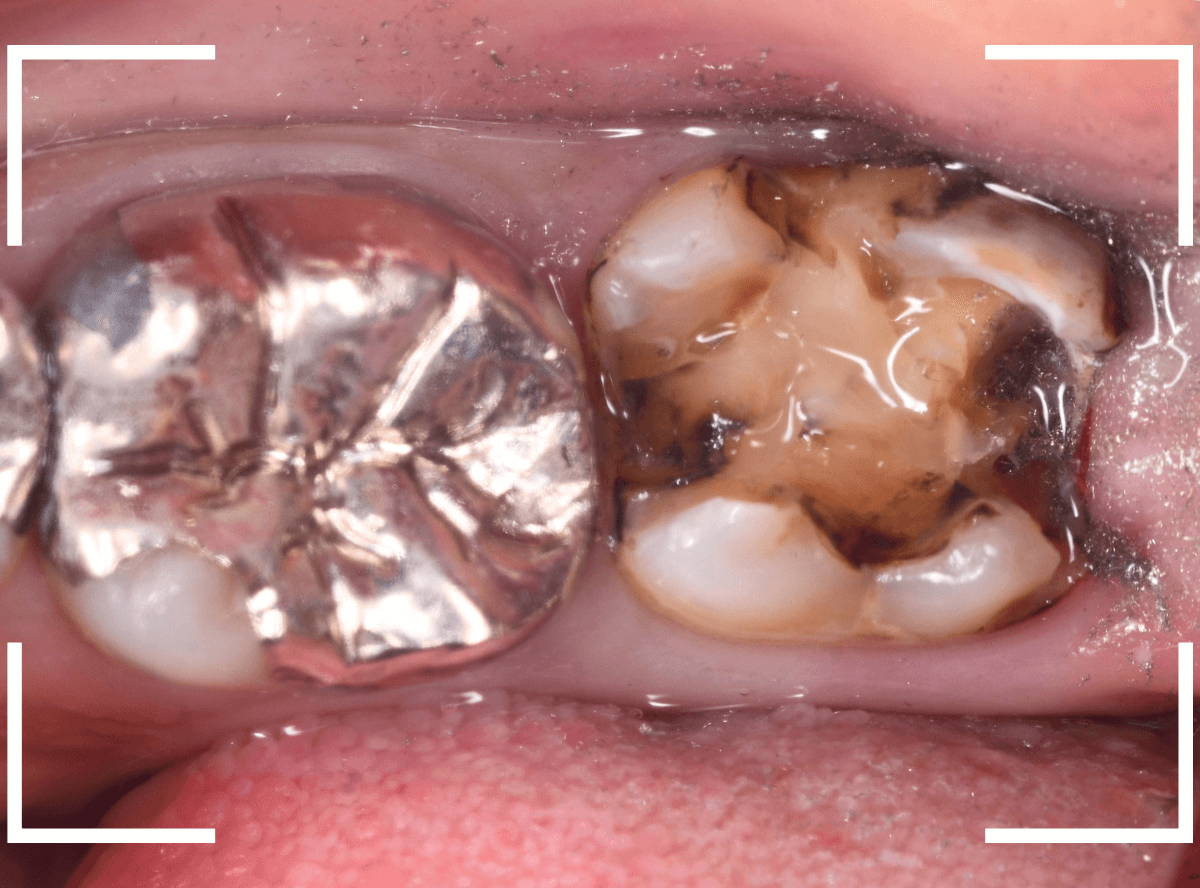

Case.16 金属の周りであちこちから虫歯

検診を希望された患者さんのケースです。

お口の中を拝見すると、上の奥歯の歯のすき間(隣接面)や、変色したレジンの中が怪しい感じです。

レントゲン写真で確認します。

青い線が神経で、赤い線が虫歯と思われる部分です。

奥から3歯が虫歯と思われますが、特に中央の歯の虫歯が深そうです。

まず、中央の歯の金属を除去します。

〇部分は前の治療時にしいたセメントです。この下に虫歯が広がっていると思われます。

セメントを除去したところです。

赤く染め出されているところが虫歯です。

神経に近くなっていますので、診療に虫歯を除去します。

側面のレジンや隣の歯との間の虫歯も慎重に除去します。

かなり広く虫歯が広がっています。

奥の歯の虫歯も全て除去しました。

3歯すべての虫歯を除去したところです。

しばらくお薬をつめて症状を経過観察した後、型どりをしてつめものを再製作する予定です。